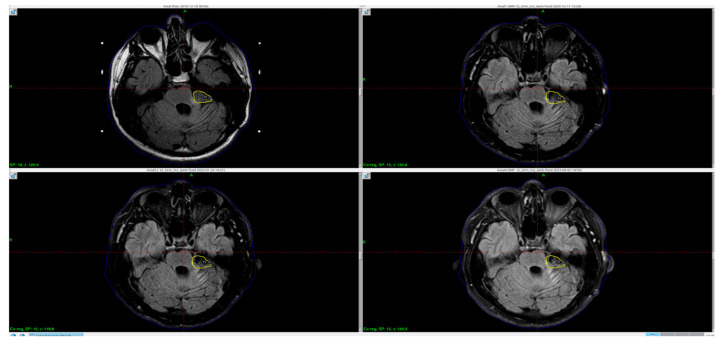

背景和临床意义:“回飞镖征”是指胼胝体脾部出现的回飞镖状细胞毒性水肿区。在MRI的t2加权图像、FLAIR和DWI上表现为高强度病变。目前还没有发现导致脾脏这些变化的具体病理机制;然而,作者列出了各种潜在的原因。病例介绍:本病例为一38岁男性患者,左脑桥小脑角肿瘤切除后,FLAIR MRI序列显示胼胝体内异常信号强度增高(回旋征)。在我们的病例中,与文献中描述的患者不同,连合的变化持续存在。结论:这些病变可能是由多种因素引起的,如小脑水肿和蛛网膜下腔出血的发展或在重症监护病房使用高渗盐。

Background and Clinical Significance: The term "boomerang sign" refers to a boomerang-shaped area of cytotoxic edema in the splenium of the corpus callosum. It is seen as hyperintense lesions on T2-weighted images, FLAIR and DWI in MRI. No specific pathomechanism leading to these changes in the splenium have been yet found; however, authors have listed a variety of potential causes. Case Presentation: The case presents a 38-year-old male patient after left cerebellopontine angle tumor resection with an abnormal, increased signal intensity within the corpus callosum (boomerang sign) in FLAIR MRI sequence. In the case of our patient, unlike the patients described in the literature, the changes in the commissure persist. Conclusions: These lesions could be caused by several factors such as the development of cerebellar edema and subarachnoid bleeding or hypertonic salt usage while in the intensive care unit.